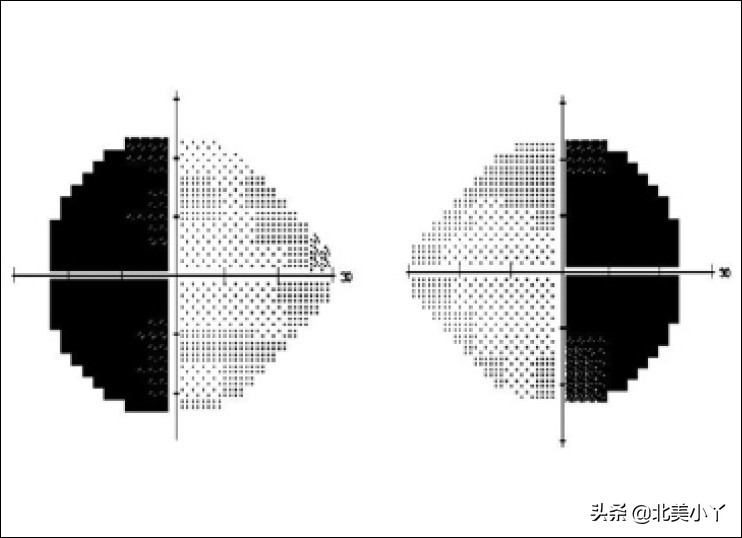

”头疼“、”恶心呕吐“、”看东西模糊“、”双耳侧余光看不见东西(视野缺损)“、”性功能低下“、”性欲下降“、”没有月经(闭经)“、”面部潮红“、”心跳加速(心脏房颤)“等等。

双颞侧(耳侧)视野缺损